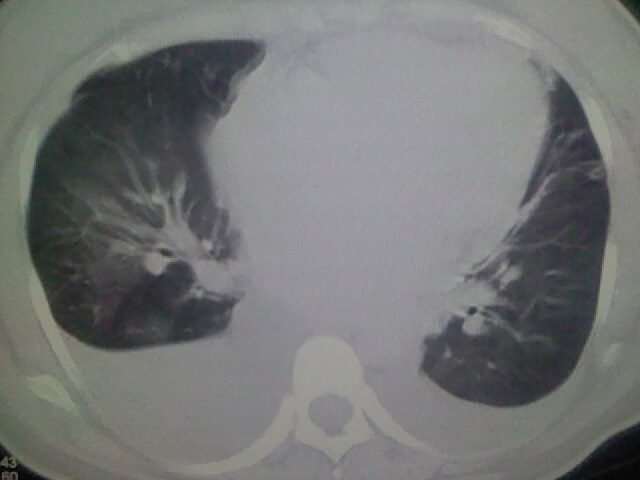

女,24,剖腹产后,突觉胸痛,干咳,不能平卧

双肺“肺泡性肺水肿” “胸腔积液”!

考虑肺梗塞、肺水肿,双侧胸腔积液

考虑产后心肌病,心功能不全,肺水肿,双侧胸腔积液。

考虑产后心肌病,心功能不全,肺水肿,双侧胸腔积液。不排除羊水栓塞可能。